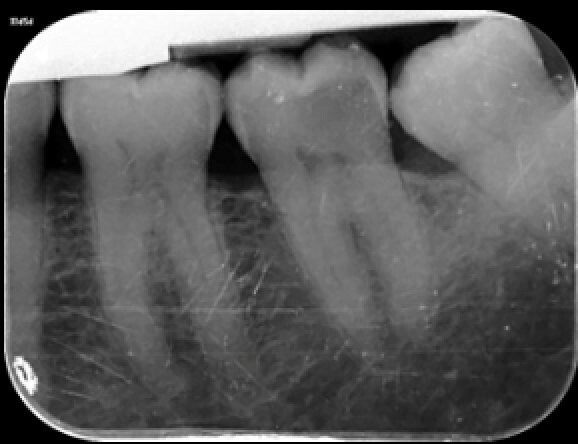

Abbildung 1: Ausgangssituation. Initiale klinische Präsentation einer ausgeprägten, kavitierten, kariösen Läsion an Zahn 37, mit Symptomen einer reversiblen Pulpitis.

Abbildung 2: Die präoperative intraorale Röntgenaufnahme von Zahn 37 zeigt die bis an die Pulpa angrenzende distale Ausdehnung der kariösen Läsion.